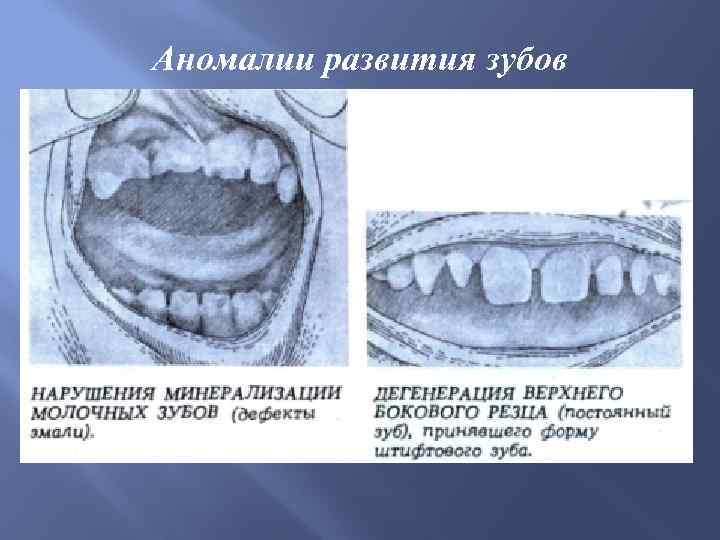

Аномалии развития зубов

Аномалии развития зубов